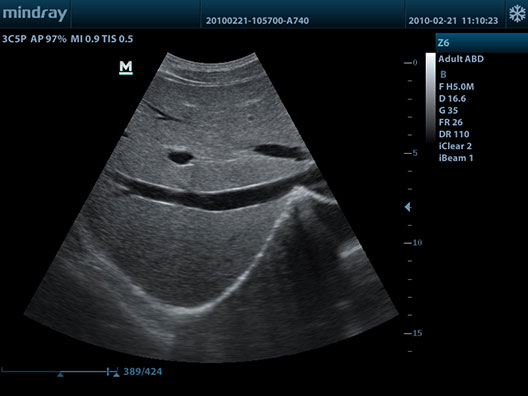

Se dispone de un Ecógrafo Mindray Z6 multifrecuencia de última generación con gran definición y resolución de imágenes.